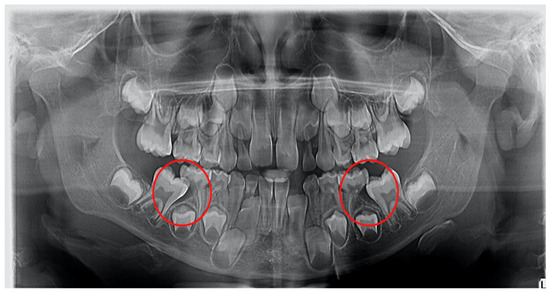

1. Introduction

2. Materials and Methods

2.3. Radiological Examination